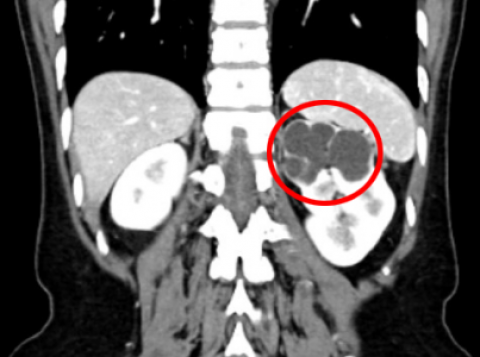

潮安78岁奶奶乘上 “健康快车”,在中山七院幸运保肾

还未出生,就发现肾脏鼓成“球”?肾积水胎儿嘟嘟踏上冒险之旅